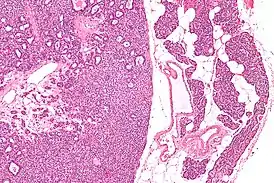

![]() Микропрепарат: аденома паращитовидной железы слева, справа — неизменённая ткань паращитовидной железы. | |

Микропрепарат аденомы паращитовидной железы.